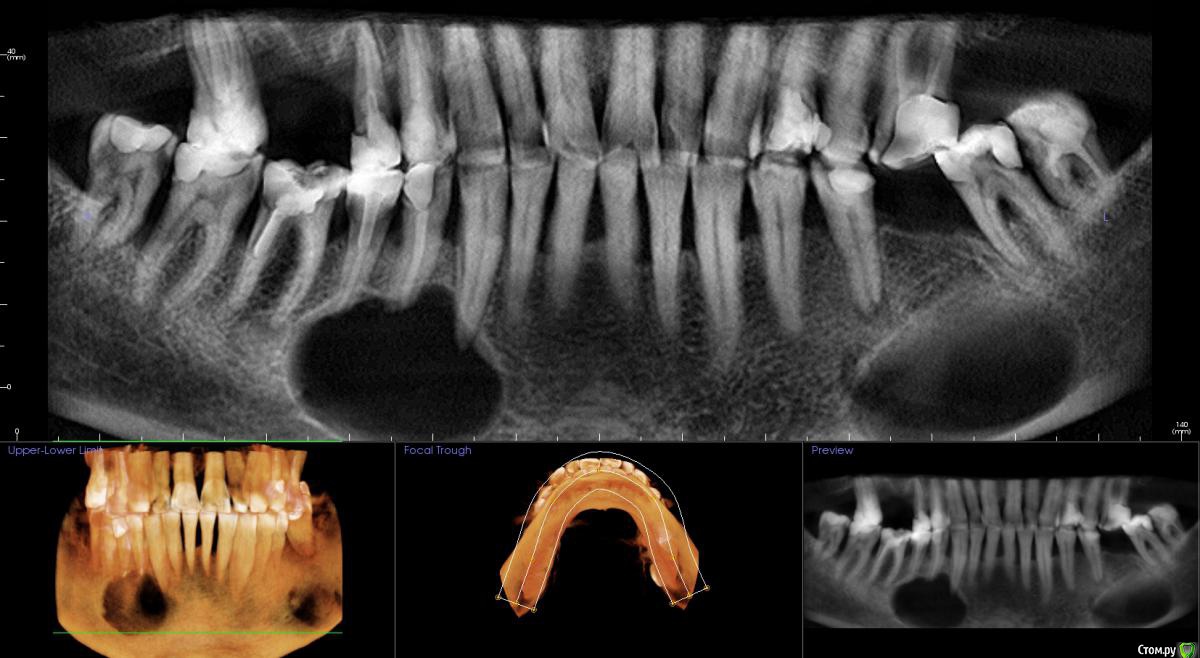

kamranchick Опубликовано 1 сентября, 2015 Поделиться Опубликовано 1 сентября, 2015 Не подскажите что с пациентом? пришел ставить мосты снизу и сверху, отправили на ОРТО, а тут такое... Ссылка на комментарий

kamranchick Опубликовано 2 сентября, 2015 Автор Поделиться Опубликовано 2 сентября, 2015 Артефакт наверное)сначала прицельный сделали, потом панорамный, потом на кт, везде одна и та же картина была Ссылка на комментарий

JDS Опубликовано 2 сентября, 2015 Поделиться Опубликовано 2 сентября, 2015 А может обширная генерализованная радикулярная киста?? Слева будто резидуальная. Не буду тыкать в небо, дождемся ответа опытных))) Ссылка на комментарий

pigmaleon Опубликовано 2 сентября, 2015 Поделиться Опубликовано 2 сентября, 2015 Радикулярная и резидуальная кисты. 1 Ссылка на комментарий

major Опубликовано 2 сентября, 2015 Поделиться Опубликовано 2 сентября, 2015 В ЧЛХ. Там ребята если не будут подстраховываться(биопсия и т.д.) прооперируют с формированием дефекта или без. Скорее всего остеосинтез пластинами планироваться будет возможно + костные блоки из гребня подвздошной. Возможен дистракционный остеогенез, если будет дефект. Заинтересованные зубы удаляются.Онконастороженность никто не отменял))) Материал на гистологию конечно же. Ссылка на комментарий